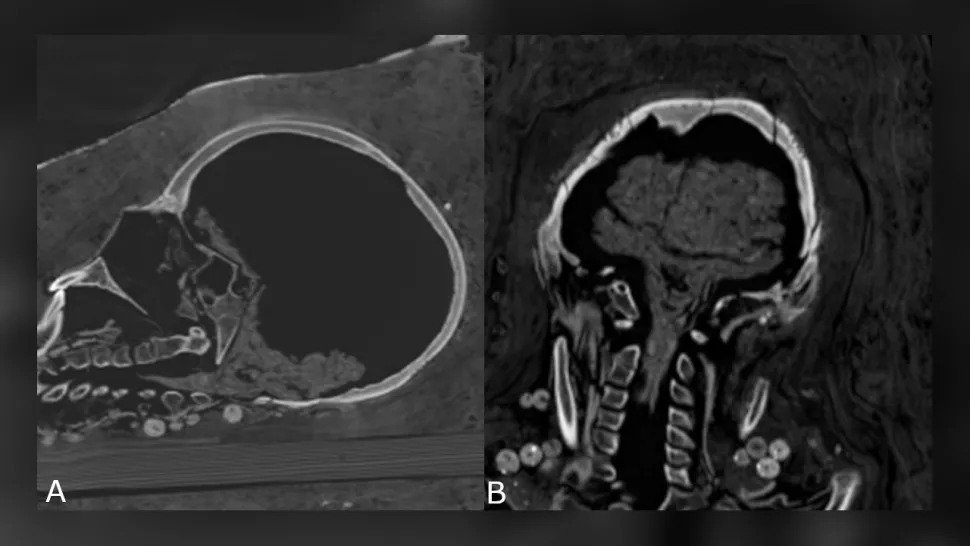

The woman's brain was not preserved either, but the adolescent's brain was preserved – it had shrunk, but the brain and brainstem could still be identified – and other internal organs of the adolescent were also present.

Shrinking teen brain. (Zesh et al., PLOS One, 2020)

The woman, who died between the ages of 30 and 40, was about 151 cm tall. She had advanced arthritis in the left knee. The teenager, according to computed tomography, died between the ages of 17 and 19 and was about 156 cm tall.

According to the researchers, she had a benign tumor in her spine known as vertebral hemangioma, which is more common in people over 40.